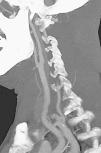

Fig. 3. --(A) Imagen de reconstrucción volumen rendering. (B) Reconstrucción mini-MIP de la arteria carótida izquierda. Estudio de angio-CT donde se observa la bifurcación carotídea y la porción proximal de ACI sin ninguna estenosis de significación.